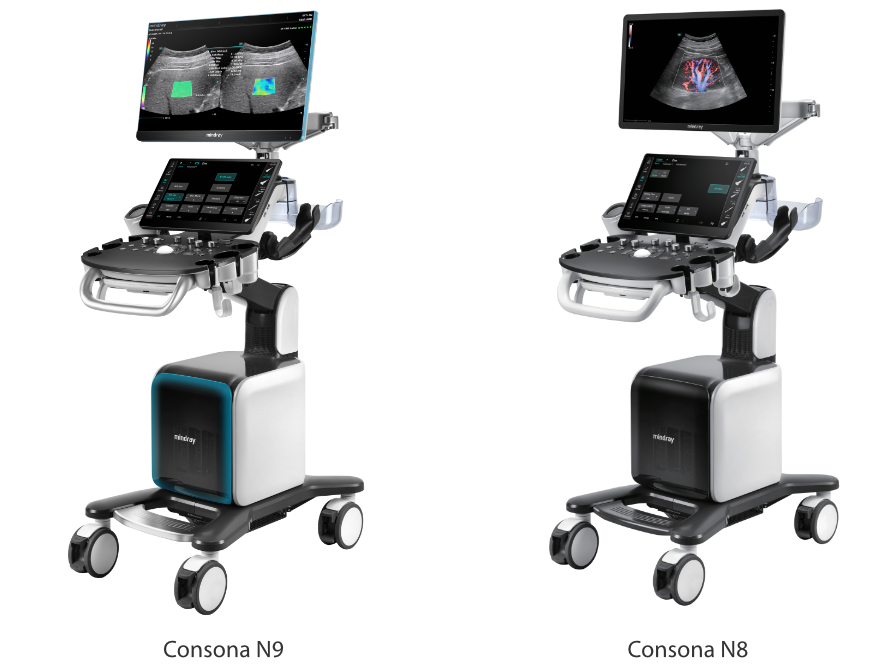

Dise?ado especĂficamente para usuarios de atenciĂłn primaria, el equipo Consona presenta soluciones nuevas y concretas que lo ayudan a realizar diagnĂłsticos sin problemas y de manera eficiente en diversos tipos de pacientes.

Independientemente de si lleva a cabo su rutina en hospitales o clĂnicas, o si estĂĄ perfeccionando sus habilidades en aplicaciones de diagnĂłstico por imĂĄgenes generales, atenciĂłn de la salud de la mujer o especialidades cardiovasculares, esta serie dispone de herramientas muy potentes para que se mantenga a la vanguardia.

Transductores